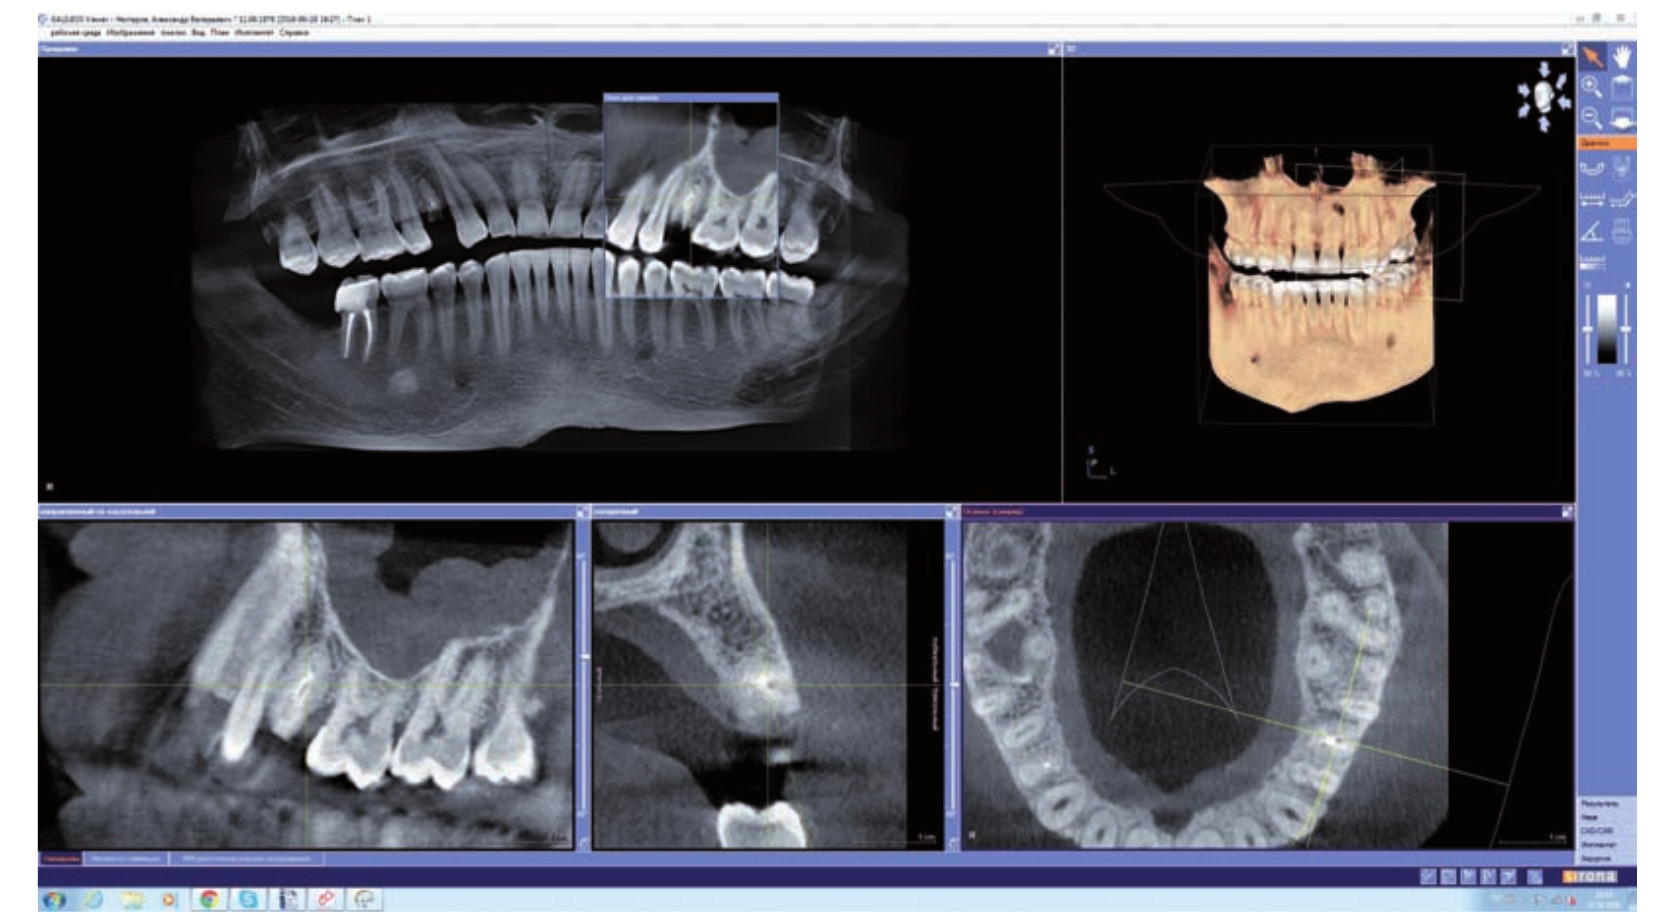

Наверняка вы слышали об искусственном интеллекте в разных сферах нашей жизни – от беспилотных автомобилей до рекомендательных систем в онлайн-магазинах. В стоматологии ИИ – это программное обеспечение, способное анализировать медицинские изображения (компьютерную томографию, рентгеновские снимки), выявлять патологии, планировать хирургические вмешательства и даже прогнозировать результаты лечения. В основе работы ИИ лежат сложные алгоритмы машинного обучения, которые обучаются на огромных массивах данных, чтобы распознавать закономерности и делать прогнозы.

Представьте себе, что у вас есть виртуальный ассистент, который способен проанализировать КТ снимок челюсти и за считанные секунды определить оптимальное место для установки имплантата, учитывая плотность кости, расположение нервов и анатомические особенности пациента. Это не фантастика, а реальность, которая становится все более доступной благодаря развитию технологий ИИ.

- Анализ КТ снимков: ИИ анализирует КТ снимки челюсти, выявляет области с достаточной плотностью кости, определяет расположение нервов и сосудов, а также выявляет патологии, такие как кисты или опухоли.

- Виртуальное планирование установки имплантатов: На основе анализа КТ снимков, ИИ предлагает оптимальное положение имплантатов, учитывая все анатомические особенности пациента. Мы можем виртуально установить имплантаты в 3D модели челюсти и оценить результаты.